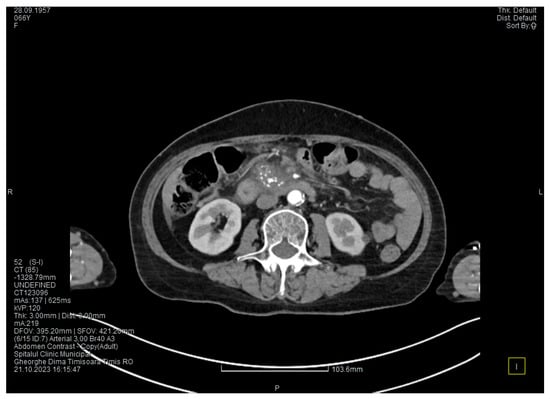

The contrast-enhanced computed tomography showed changes suggestive of chronic pancreatitis, with multiple very small calcifications of the pancreatic tissue, dilatation of the Wirsung duct in the corporeo-caudal area measuring approximately 15 mm (Figure 3), and a narrowing of the Wirsung tract in the cephalic area where calcareous conglomerates were present. In the anterior cephalo-uncinate area, an oval cyst measuring 31/28 mm was detected (larger than it was one month ago) (Figure 4). In the peri-cephalo-uncinate area, we observed densifications of the adjacent fat extending towards the gastric antrum, the root of the mesentery, and the hepatic flexure of the colon. There was a mild inflammatory enlargement of the peripancreatic lymph nodes and the ones situated in the hepatic hilum. We also noticed a slight dilatation of the intrahepatic bile ducts and the common hepatic duct, and diffuse atheromatosis of the aorta, the iliac, and the common hepatic arteries. We performed a gastroscopy, which revealed a normal esophagus, stomach, and duodenal bulb; however, it was impossible to advance the endoscope towards the D2 part of the duodenum due to the significant edema of the duodenal mucosa and the partial stenosis of the duodenal lumen.

Figure 3. The second CT evaluation shows a dilated Wirsung duct and calcifications in the pancreatic tissue.

Figure 4. The second CT scan shows a cyst in the pancreatic head and calcifications in the pancreatic head and groove area.